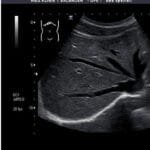

Hand held Scanner

Choice of probes and display methods, cart etc

Designed for ease of operation, these scanners can be utilized for abdominal or small part scans effectively. With a variety of probes and applications available, they are tailored to meet diverse medical needs. Whether in a clinic or a remote location, medical professionals benefit from their versatility. The conventional image footprint they provide remains crucial in various diagnostic contexts, ensuring consistency in imaging across different scenarios.